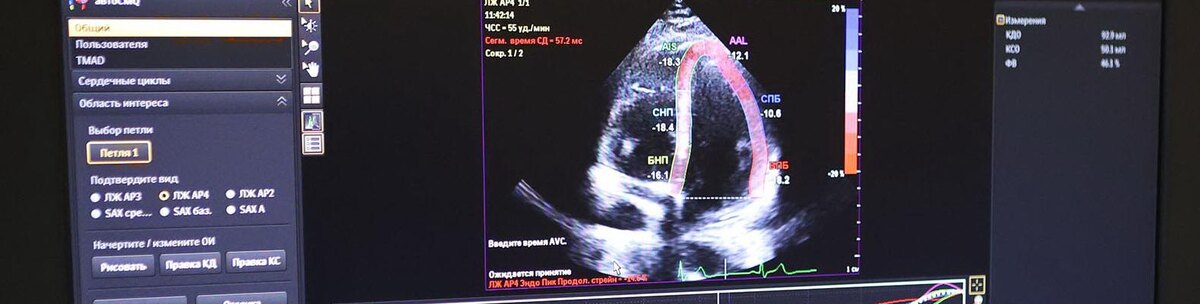

Фото: Антон Вергун